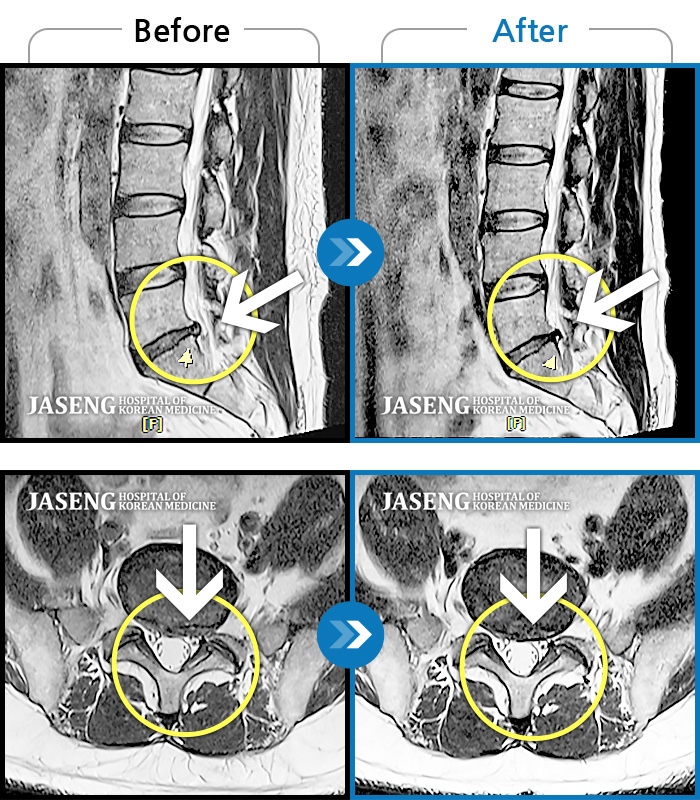

허리디스크

도움받은 사례

광주 · 장영우 원장

양측 허리부터 좌측 다리까지 이어지는 저림과 통증으로 걷기 힘들어 내원하였습니다.

촬영시기

2024.11.22 ~ 2025.05.16

2025.05.30